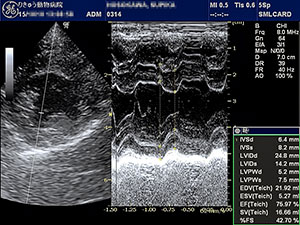

昨今、日本の犬猫たちは益々長寿になってきていますが、それに伴って多くなってきた病気の一つが心臓病です。心臓病にも様々ありますが、フィラリア寄生虫が引き起こす心臓病や栄養欠乏によって生じる心臓病は予防学、栄養学が発展した現在では過去のものとなり、今最もポピュラーな心臓病が「僧房弁閉鎖不全症」です。 僧房弁は心臓の左心房と左心室を仕切る弁です。その僧房弁が、十分に閉じなくなってしまうと、本来ならば一方通行であるはずの心臓内の血液に逆流が生じ、血液がうまく流れなくなってしまうことで、初期には咳、中期以降は肺水腫や失神などの症状を引き起こす疾患です。

犬で最も多くみられる後天性心疾患の一つで、マルチーズ、ヨークシャー・テリア、トイ・プードル、シー・ズー、チワワなどの小型犬の中齢期以降に多くみられます。ただしキャバリア・キング・チャールズ・スパニエルは、若齢時から進行していく傾向がありますのでキャバリアさんの飼い主様は重々注意してください。

この疾患の最も多い原因は、加齢に伴う僧房弁の粘液腫様変性による弁尖の変形、ゆがみ、逸脱などによって、僧房弁の閉鎖が障害されてしまうことです。他には、心室中隔欠損、動脈管開存症、拡張型心筋症などによる左心室の拡大によって、僧帽弁輪が拡大してしまい、うまく閉まらなくなった結果、血液の逆流が生じることもあります。診断は聴診、胸部レントゲン検査、心エコー検査などを使い評価していきます。

心臓病は高齢の動物に発生しやすい病気ですが、幼い子にも発生します。ただし、幼い子の心臓病は僧帽弁が変性してしまう「僧房弁閉鎖不全症」ではなくて、その多くは先天的、つまり生まれ持った構造異常に起因しています。今回は先天性心疾患のひとつ、「心室中隔欠損症」を紹介します。

心室中隔というのは、左心室と右心室を仕切っている壁です。心室中隔欠損症では、このしきりである心室中隔に、生まれつき欠損孔(穴)が存在してします。そうすると、左心室と右心室の間に血液短絡(バイパス)ができてしまい、通常の血液循環と異なるために、トラブルを生じる心疾患です。犬ではあまり多くはないですが、ミニチュア・ダックスフンド、フレンチ・ブルドックなどの犬種で見られることがあります。猫では、一般的にみられる先天性心疾患です。診断は聴診、胸部レントゲン検査、心エコー検査などで行います。

心室中隔欠損では、

1. 欠損孔の大きさ・位置、2. 短絡する血流の方向や速度、3. 房室弁や大動脈弁逆流などの合併症

などにより、予後が大きく異なります。

特に心エコー検査では、心臓の弁の状態や、血流の速さ・向きなどをリアルタイムで見ることができるため、当院では主にこの心エコー検査による心臓の評価に重点をおいています。